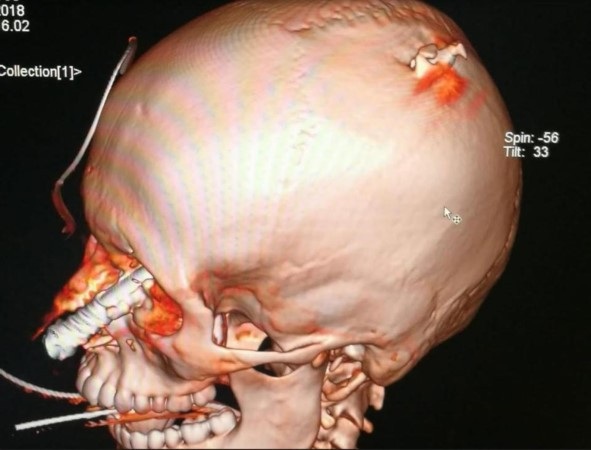

Devon White 14 tuổi, đến từ Chelmsford, Essex đã bị thanh lao đâm xuyên qua mắt trong khi đi nghỉ ở Ý cùng gia đình. Cảnh sát cho biết cây súng phóng lao sắc nhọn đã bị hỏng chốt và không được khóa đúng cách nên khi White đứng lên, ngọn lao bắn luôn vào đầu cậu bé.

Đây là một cuộc phẫu thuật rất hiếm và không phổ biến. Tôi từng xử lý vết thương do dao đâm, nổ súng, tai nạn xe hơi nhưng chưa bao giờ thực hiện cho một cậu bé 14 tuổi với một thanh thép cắm sâu 30 cm trong đầu mình. Cậu bé đã quá may mắn vì thanh thép đi qua khoang sau của mắt, xuyên qua xương đỉnh. Đó là phần trên của hộp sọ và bảo vệ bộ não”, bác sĩ chủ trì ca phẫu thuật Alberto Delitala, 66 tuổi chia sẻ.

Bác sĩ cũng cho biết phần tinh vi nhất của ca phẫu thuật là loại bỏ thanh thép một cách hoàn toàn mà không gây thêm bất cứ thiệt hại nào cho não bộ. Trước khi tiến hành phẫu thuật, đội cứu hộ cũng đã cắt bớt một nửa thanh thép đi.